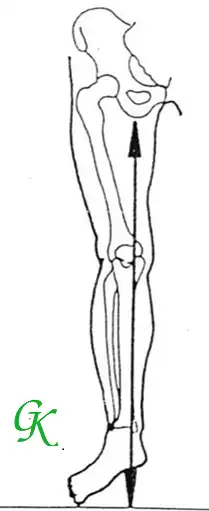

- Nẹp Chỉnh hình với chức năng DẪN HƯỚNG VẬN ĐỘNG: Các chi thể bị lệch trục và biến dạng không cho phép bệnh nhân đi lại bình thường. Bên cạnh việc ổn định khớp, một điều vô cùng quan trọng nữa là Nẹp sẽ dẫn các cử động theo đúng hướng mong muốn. Điều này làm cho dáng đi được an toàn, tự nhiên hơn và năng lượng liên quan được sử dụng hiệu quả.

- Nẹp với chức năng CỐ ĐỊNH: với mục đích giữ ổn định cơ thể ở vị trí tốt và dẫn hướng cho sự phát triển. Tình trạng các cơ, nhóm cơ quá yếu_không đủ lực để ổn định (làm vững vàng các khớp), người bệnh thậm chí không tự đứng vững được thì Nẹp chỉnh hình sẽ hỗ trợ, làm cho bệnh nhân đứng thẳng và đi lại được.